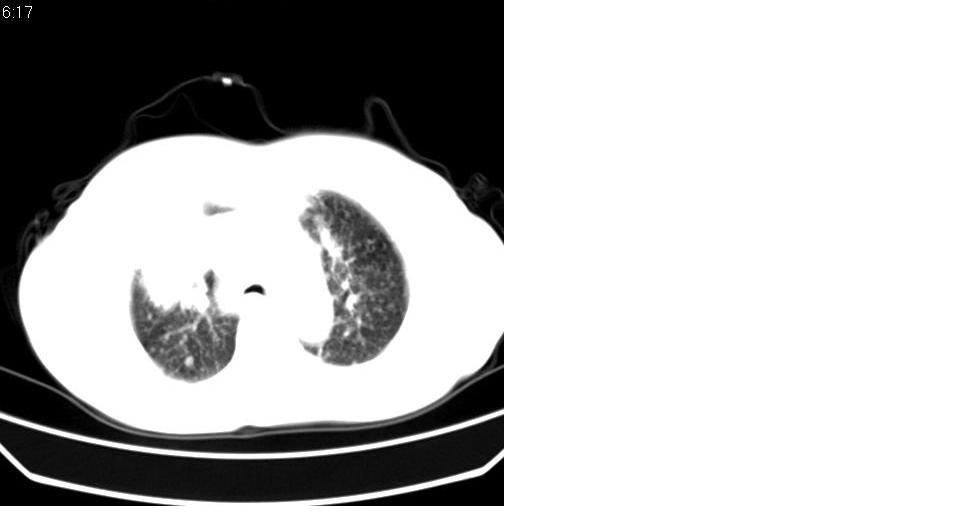

标题: CT16839:胸部CT平扫

女 50岁,在其他医院确诊肺癌.

肺癌并肺内及纵隔淋巴结转移

考虑 肺癌伴肺及纵隔转移,心包膜增厚